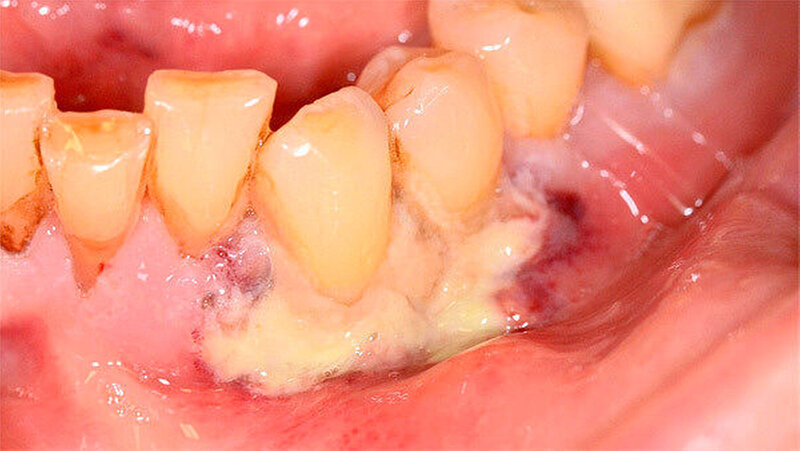

Nach 48 Stunden i.v.-Antibiose und intensiver Hygienisierung (Abbildung 3) erfolgte die Abtragung der Gingivanekrose unter laufender Dabigatran-Medikation. Die sich von Zahn 32 bis 35 vestibulär und interdental erstreckende Nekrose wurde schonend entfernt (Abbildung 4). Eine Mitbeteiligung des Alveolarknochens war nicht erkennbar. Im Anschluss erfolgte eine chemische Dekontamination der Wunde mit Betaisodona-Lösung sowie der primäre Wundverschluss mittels modifiziertem koronalen Verschiebelappen (Nahtmaterial: Resolon 4.0, Resorba Medical GmbH). Die Zähne 32 bis 34 wurden aufgrund ihrer geringgradigen Lockerung belassen und mittels Säure-Ätz-Technik primär durch Schienung stabilisiert. Abschließend erfolgte die Abdeckung des OP-Situs mit einer Verbandsplatte, in welche im vestibulären Bereich eine Aussparung eingearbeitet wurde (Abbildung 5).